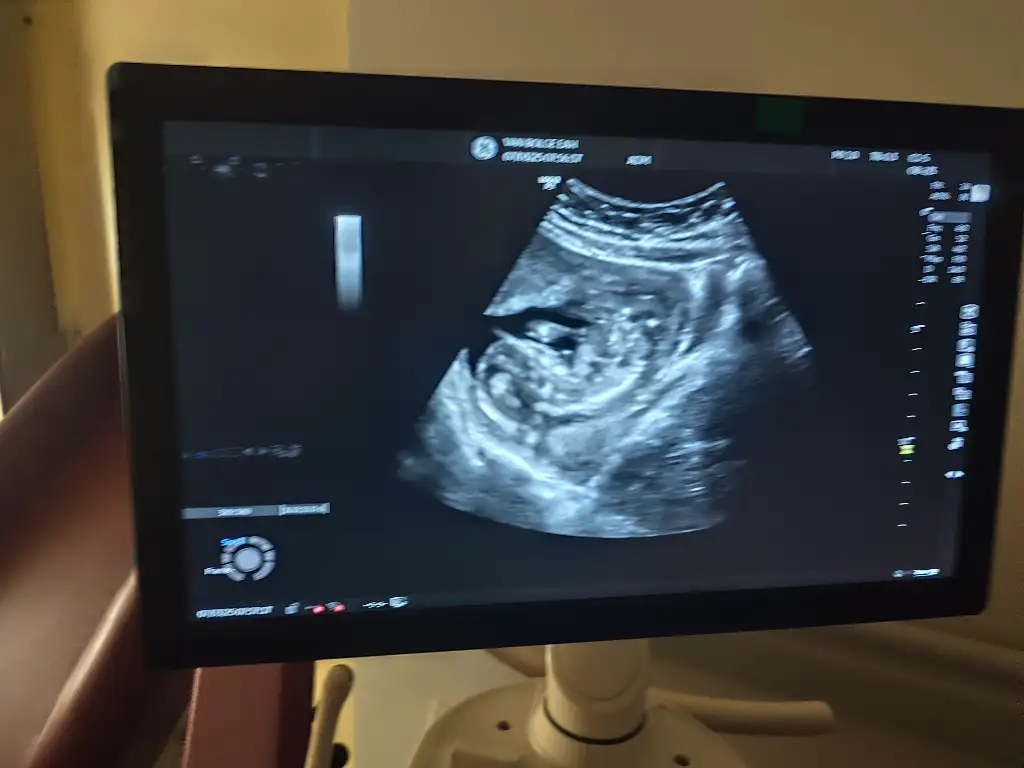

Arkadaşlar benim bebişime de bakar mısınız 16 haftalik